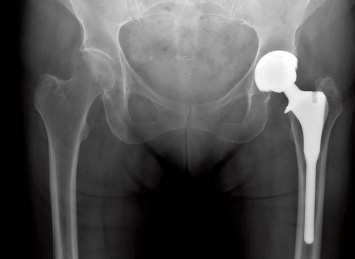

| | Hip Replacements Have Skyrocketed: The number of hip replacements performed in the U.S. has increased substantially, and the procedure has become more common in younger people. HealthDay, Feb. 12.